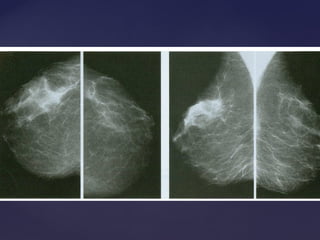

Padrão mamográficoPadrão mamográfico

Descrição Acurácia Diagnóstica

Lipossubstituídas (até 25% de tecido

glandular)

Muito alta

Parcialmente lipossubstituídas (26 a 50% de

tecido glandular)

Alta

Densas e heterogêneas

(51 a 75% de tecido glandular)

Limitada

Muito densas (>75% de tecido glandular) Limitada